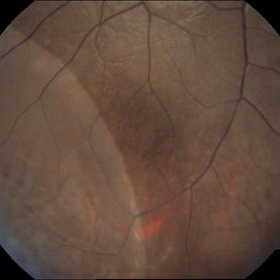

Age-Related Macular Degeneration

Sep 10 2014 by Mehul A Shah

65-year-old female presented with sudden loss of vision.

Photographer: Drashti Netralaya, Dahod

Imaging device: FF 450

Condition/keywords: age-related macular degeneration (AMD)